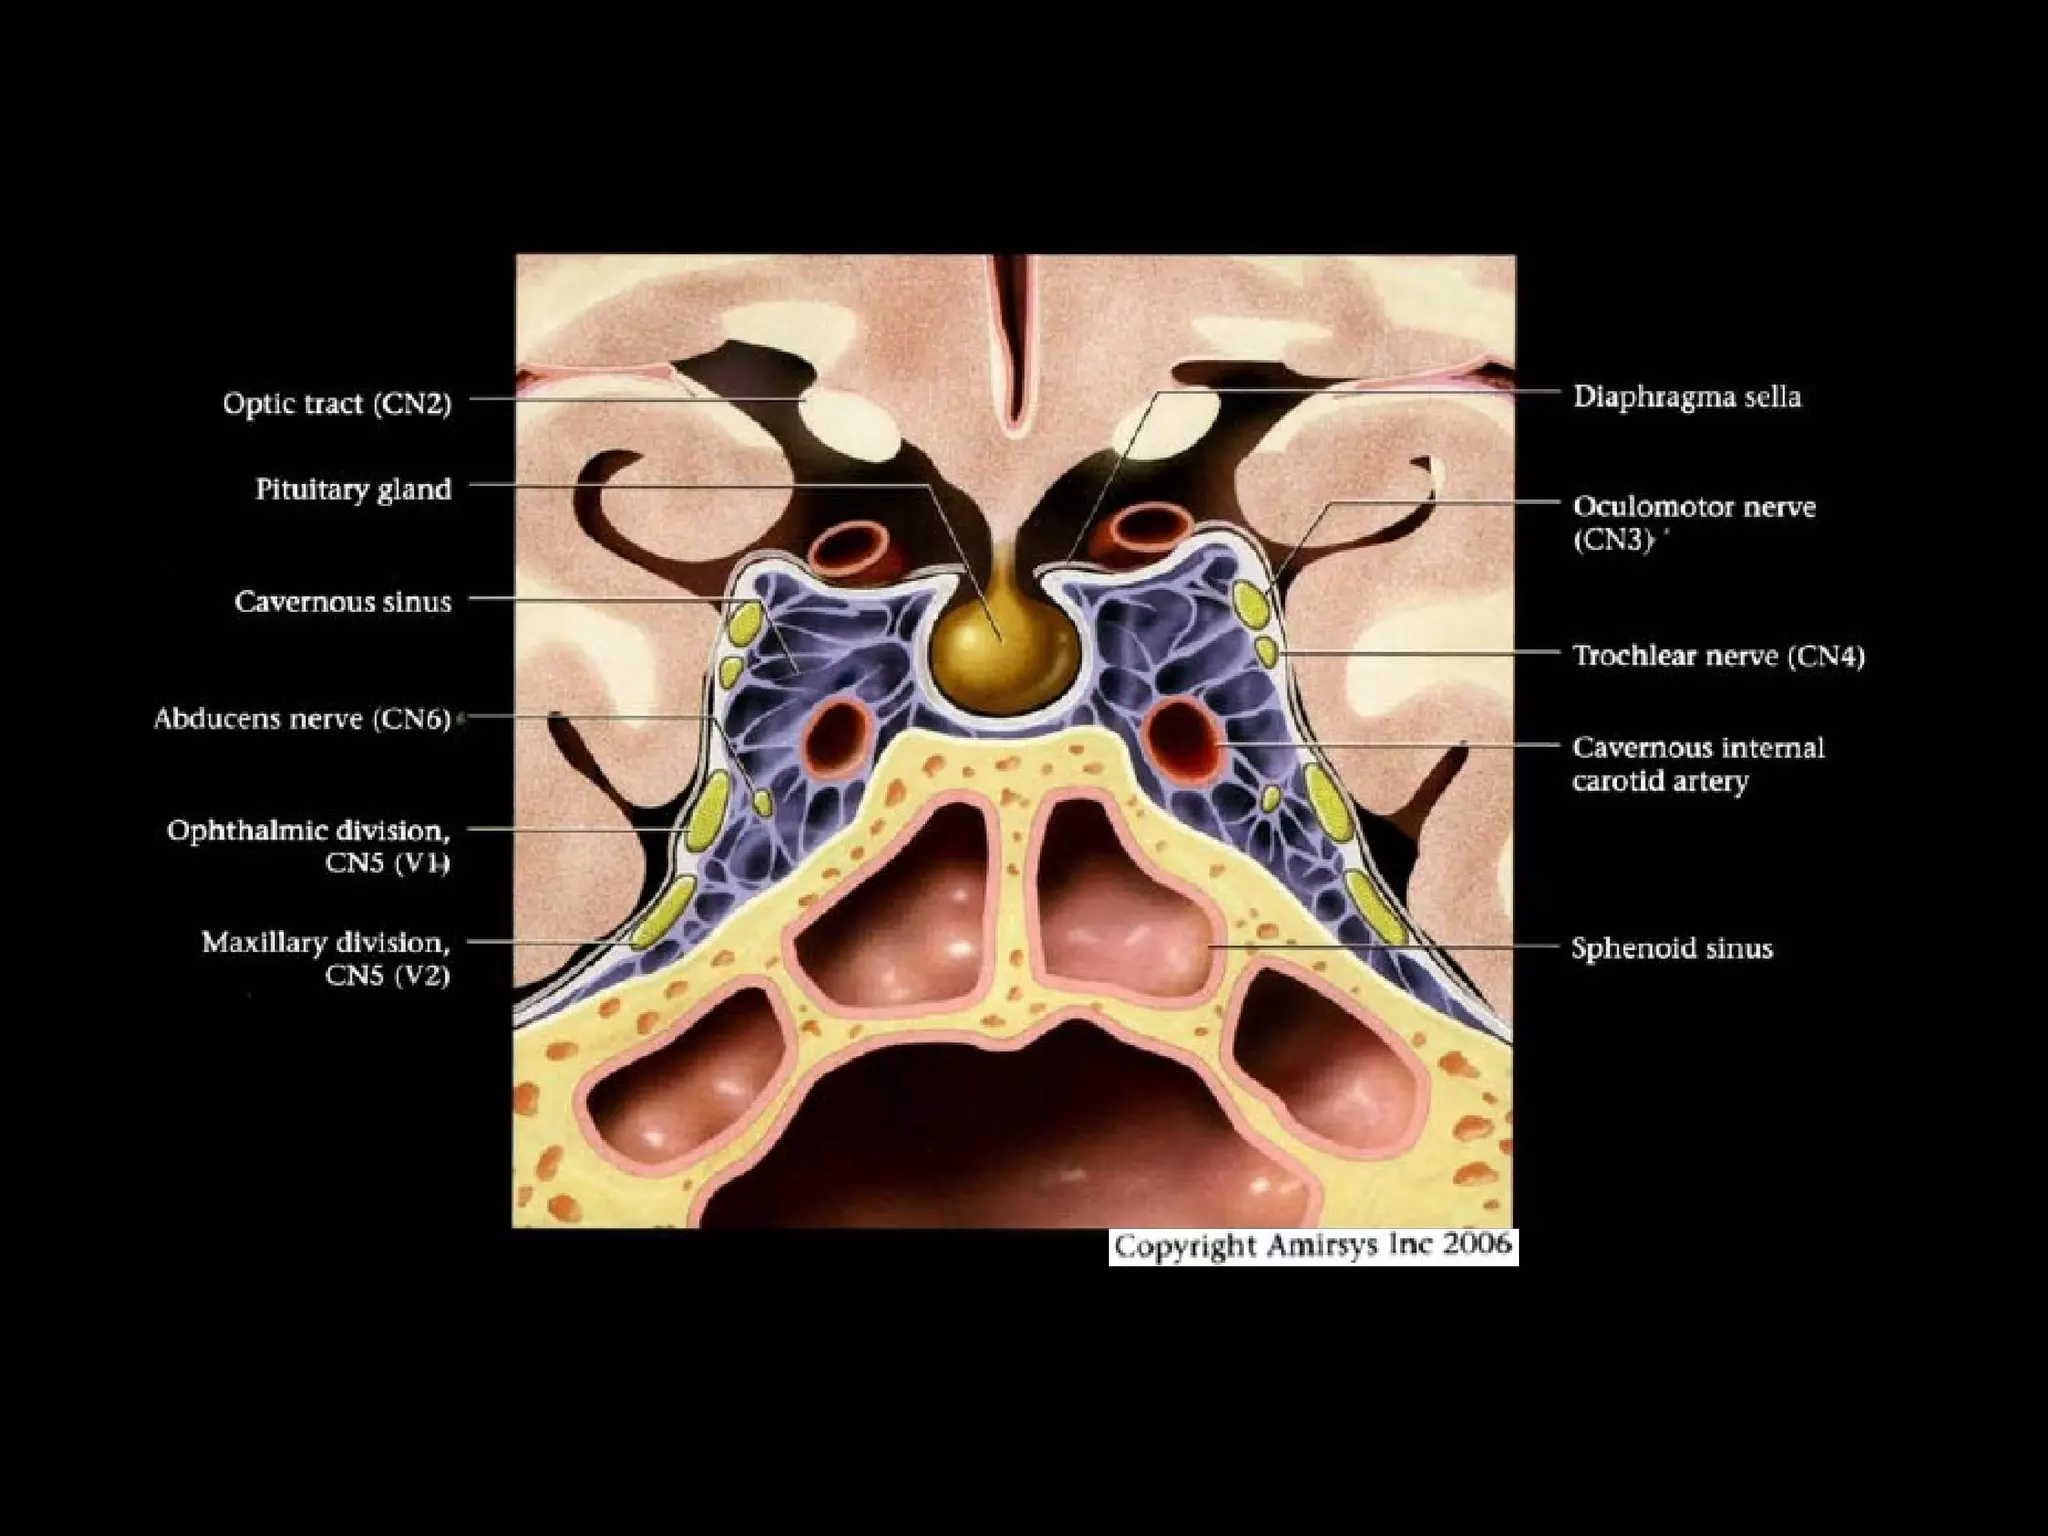

Cavernous Segment

• Courses anteriorly through lateral dural

wall of cavernous sinus

• Intracavernous relationships of CN4

- Remains inferior to CN3

- Superior to ophthalmic division of

trigeminal nerve (CNV1)

- Lateral to cavernous internal carotid

artery

• CN6 courses anteriorly within cavernous sinus

- Abducens nerve is only cranial nerve to lie

within cavernous sinus

- Cranial nerves 3, 4, VI and V2 are all

embedded within lateral wall of cavernous sinus

• Within cavernous sinus CN6 runs along

inferolateral aspect of cavernous internal carotid